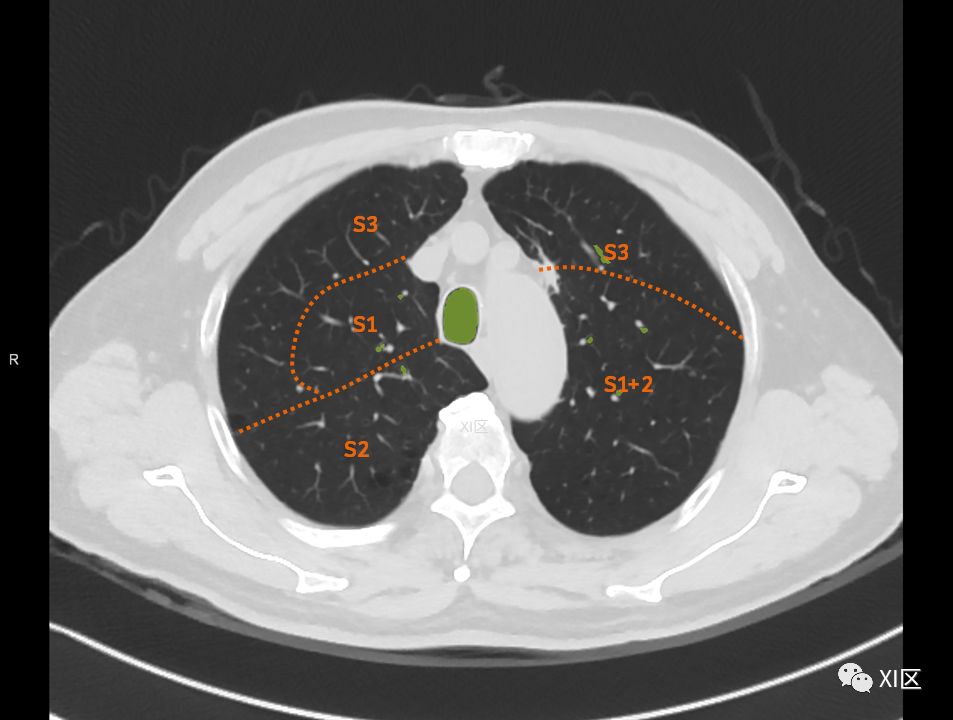

肺的断层分段示意图

在进行肺的分段时,可以上下观察浏览,沿着相应气管的走形可以更容易准确地进行分段。